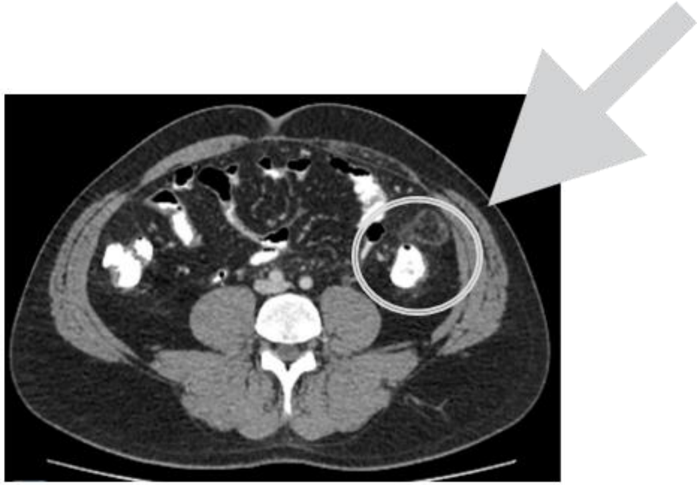

Homem, 47 anos, se apresenta ao Pronto Socorro com dor em fossa ilíaca esquerda há 1 dia sem febre ou demais sintomas. Nega episódios semelhantes ou cirurgias prévias. No exame físico, está em bom estado geral, normocárdico, afebril, abdome flácido, com dor localizada em fossa ilíaca esquerda, sem dor à descompressão brusca. Hemoglobina 14,8 g/dL (normal 12-16g/dL), Leucócitos 8750 s/ desvio (normal 6-10 mil), Proteína C Reativa 9 mg/L (normal até 5 mg/L). Realizada Tomografia, que observou a seguinte imagem.

Aponte o tratamento mais adequado: